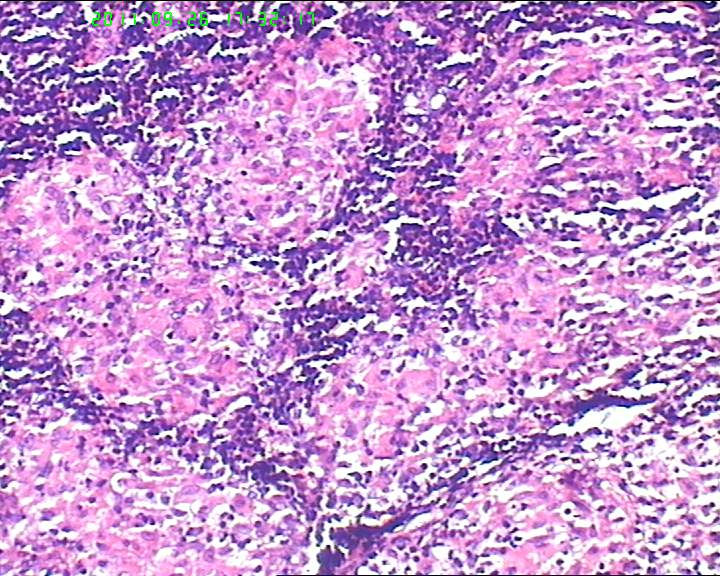

21岁女性左侧颌下淋巴结,该诊断什么?

灰白不整形肿物一个,大小3.5*2.5*2cm,包膜完整。

21岁女性左侧颌下淋巴结,该诊断什么?图2

慢性肉芽肿性炎症,形态学倾向结节病,但是作为病理工作者对于这样的病例,再结合咋们国情,还是建议临床除外增殖性结核后再考虑结节病。

肉芽肿性炎症,倾向结节病。